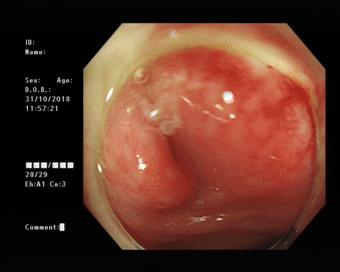

做好肠道准备后于31日上午在内镜室进行了内镜下逆行阑尾炎治疗术,镜下可见阑尾开口呈半月形,边缘粘膜充血、水肿,并有大量脓液流出,随在斑马导丝引导下将导管引导入阑尾腔用生理盐水进行阑尾腔反复冲洗并用替硝唑保留阑尾灌注,术后,患者自诉腹痛明显缓解。

镜下可见